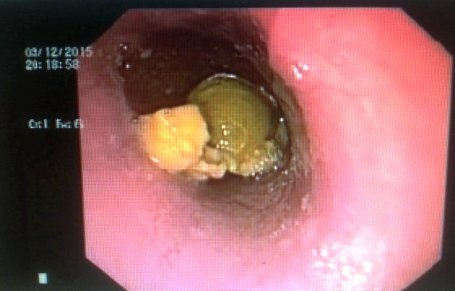

Sau khi thăm khám, các bác sĩ đã phát hiện một dị vật nằm trong đường thực quản của bệnh nhân nên đã tiến hành nội soi cấp cứu và gắp ra một túi mật heo tươi kích thước khoảng 3x4cm nằm sâu trong thực quản. Theo các bác sĩ, may mắn cho chị T., là dị vật đã tuột xuống thực quản, nếu đang còn nằm ở đường thở thì có nguy cơ tử vong cao vì tắc đường thở.